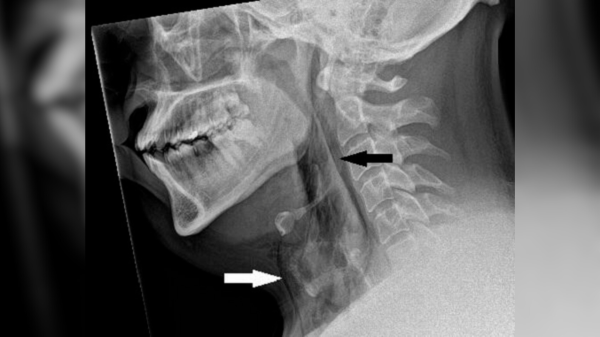

Результати розтину: Огляд черепа жінки виявив субарахноїдальний крововилив — кровотечу в просторі між мозком і шаром тканини, що його оточує. Кров накопичувалася на глибину до 6 міліметрів навколо основи мозку та стовбура мозку.

Коли судово-медичні експерти видалили згустки крові, вони виявили розірвану мішкоподібну аневризму – сферу, наповнену кров’ю, яка роздулася з кровоносної судини в мозку. Це також відоме як «ягідна аневризма» через свою схожість з круглою ягодою, що звисає з ніжки, і це найпоширеніший тип аневризми.

Аневризма мала діаметр 0,4 дюйма (11 міліметрів) і лопнула у верхній частині купола. Коли аневризми розриваються, вони викидають кров, яка може вбивати сусідні клітини мозку та підвищувати тиск усередині черепа. Зі зростанням тиску може порушитися потік кисню та крові до мозку, що може призвести до втрати свідомості та смерті. Аневризми частіше зустрічаються у жінок, ніж у чоловіків, особливо у жінок з низьким рівнем естрогену, таких як жінки в постменопаузі. Люди з гіпертонією також частіше розвивають аневризми, які розриваються та викликають кровотечу в мозку.